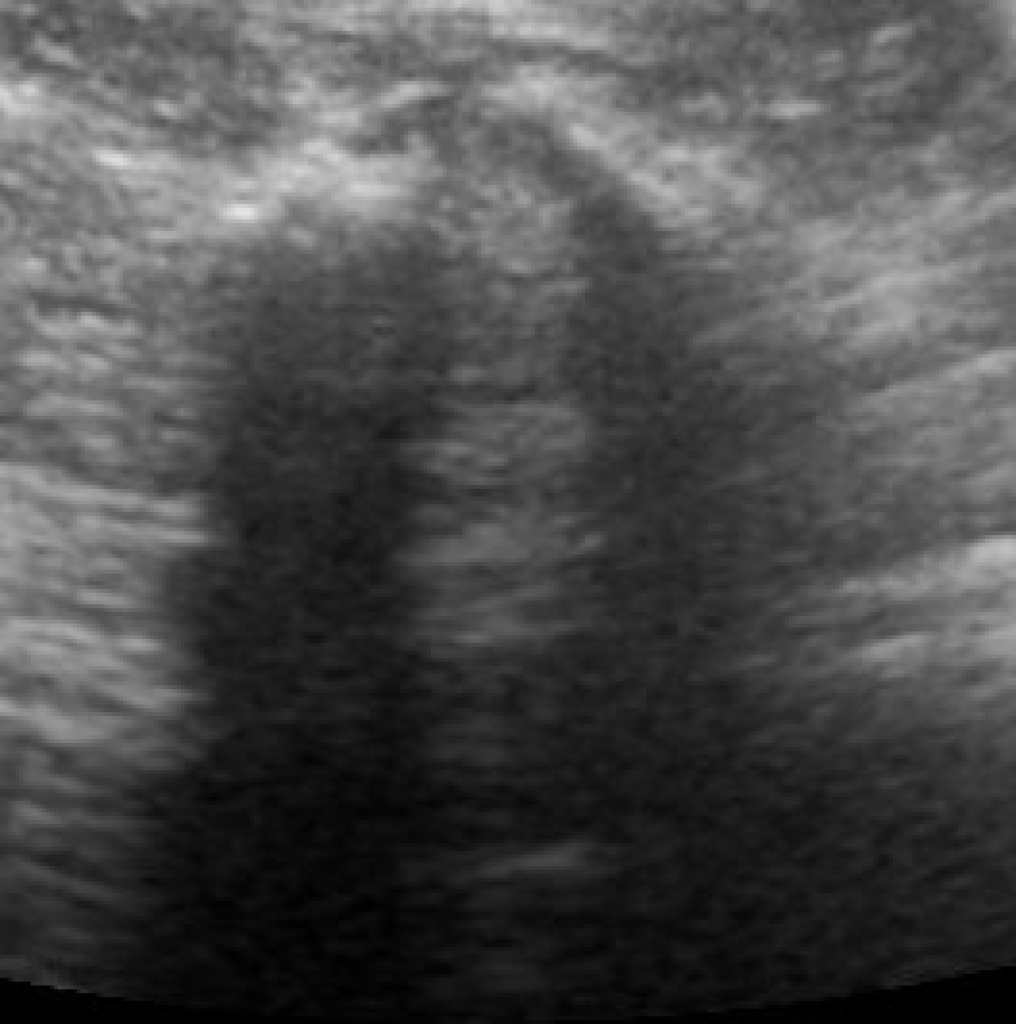

Echografie gebruiken we daarnaast vaak om iets over de synoviale structuren van het gewricht te zeggen. Zo zien we of het gewricht overvuld is en of er verdikking van het kapsel te zien is. Dit kan van belang zijn indien onduidelijk is of een gewricht met artrose op dat moment geïrriteerd is. Zo kunnen we het onderscheid maken tussen “rustige” en “actieve” problemen.

Links: Facetgewricht zoals op echobeelden

Rechts: Echobeeld van een facetgewricht

Facetgewricht zoals op echobeelden

Echobeeld van een facetgewricht